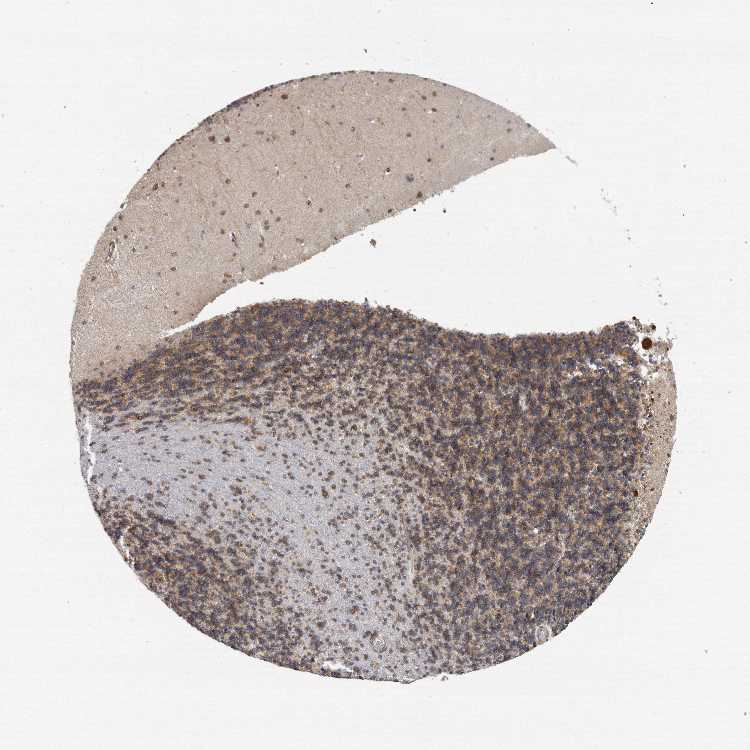

BRAIN CEREBELLUM Show tissue menu

CEREBELLUM - Antibody stainingi

Antibody staining in the annotated cell types in the current human tissue is reported as not detected, low, medium, or high, based on conventional immunohistochemistry profiling in selected tissues. This score is based on the combination of the staining intensity and fraction of stained cells.

Each image is clickable and will lead to virtual microscopy that enables deeper exploration of all samples and also displays staining intensity scores, fraction scores and subcellular localization as well as patient and tissue information for each sample.

Antibody HPA029939Antibody HPA029940

Bergmann glia - cytoplasm/membrane Medium-

Bergmann glia - nucleus Not detected-

GLUC cells - cytoplasm/membrane High-

GLUC cells - nucleus Not detected-

Purkinje cells -High

Purkinje cells - cytoplasm/membrane High-

Purkinje cells - dendrites Medium-

Purkinje cells - nucleus Not detected-

Cells in granular layer -Medium

Cells in molecular layer -Low

Granular cells - cytoplasm/membrane Medium-

Granular cells - nucleus Not detected-

Molecular layer - neuropil Not detected-

Molecular layer cells - cytoplasm/membrane Medium-

Molecular layer cells - nucleus Not detected-

Processes in granular layer Not detected-

Processes in molecular layer Not detected-

Processes in white matter Not detected-

Synaptic glomeruli - capsule Not detected-

Synaptic glomeruli - core Not detected-

White matter cells - cytoplasm/membrane Medium-

White matter cells - nucleus Not detected-